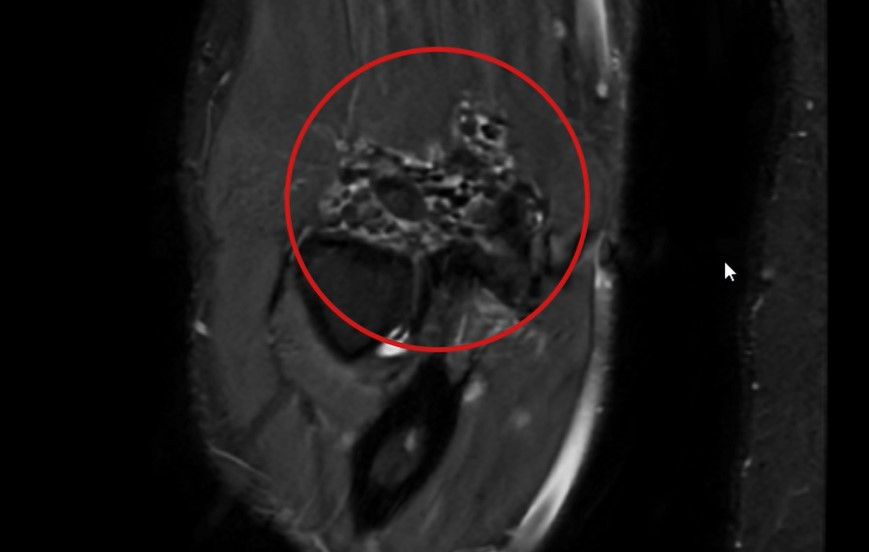

| Hình ảnh 50 viên sụn lấp đầy khớp khuỷu tay theo kết quả chụp MRI |

Theo kết quả chụp MRI, TS.BS Lê Quang Huy (Trưởng Đơn nguyên Chấn thương chỉnh hình - BVĐK Hồng Ngọc) cho biết: "Có nhiều dị vật nhỏ như những viên sỏi đường kính khoảng 0.5 - 2cm lấp đầy khớp khuỷu tay kèm cứng khớp khuỷu tư thế gấp 30 độ, xác định bệnh nhân mắc bệnh u sụn màng hoạt dịch (Synovial chondromatosis). Đây là loại u xương lành tính, hiếm gặp - tỷ lệ 1/100.000 ca, xuất hiện do sự hình thành đa khối nội khớp kèm với sự chuyển sản sụn của màng hoạt dịch (sự phát triển bất thường của cấu trúc sụn trong màng hoạt dịch). Khi vận động, các viên sụn cọ sát vào các đầu khớp khuỷu gây đau và giảm dần khả năng gấp duỗi... Vì vậy, để khôi phục vận động thì phương pháp điều trị tối ưu nhất là phẫu thuật loại bỏ toàn bộ u sụn và giải phóng khớp khuỷu”.